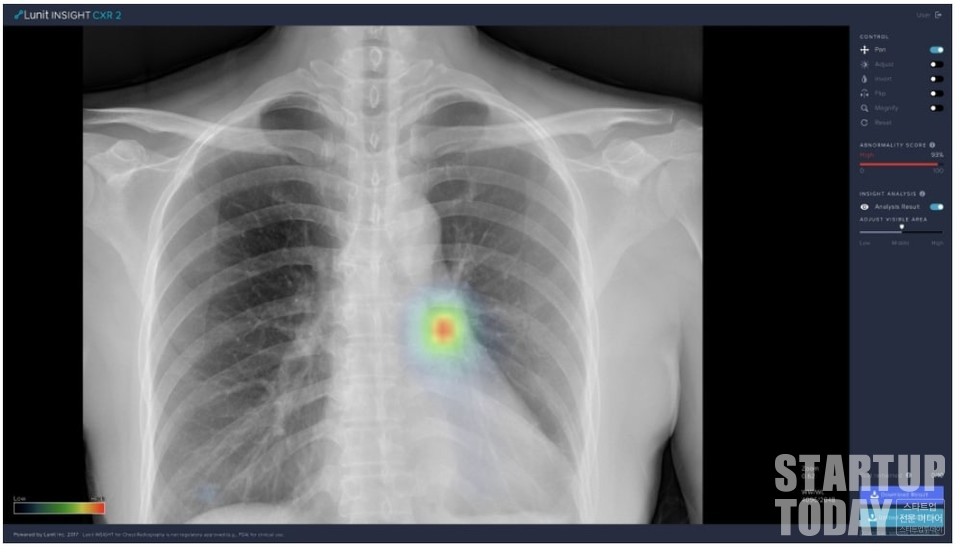

둘째, 질병의 예측과 진단을 정확하게 하는 인공지능 기술의 개발이 필요하다. 국내에도 뷰노, 루닛, 솔트룩스 등의 기업이 폐병, 척추, 팔다리골절 등 분야 빅데이터 및 인공지능 기술을 적용한 의료솔루션 개발에 집중하고 있으며 일부 선도 디지털 병원과 협력하고 있는 것으로 알려져 있다.

이 분야에서 이미 선도적으로 상당한 기간 투자를 해온 아이비엠의 왓슨 등 인공지능이 일부 우수한 성과를 내는 부분도 있다. 그러나 아직은 수많은 질병에 대한 정보 분석과 진단에 대한 완성도를 더 높이는 것이 더 필요하듯이 상대적으로 질적, 양적 측면에서 열위에 있다고 할 수 있는 우리나라 의료솔루션 기업들의 신기술 개발에 더 많은 투자와 노력이 요구된다.

특정 질병에 대한 진단결과가 나오게 되면 이것이 어떻게 도출됐는지에 대해 의사뿐만 아니라 환자에게도 설명해 신뢰를 받을 수 있는 수준의 기술이 필요하다. 특히 글로벌 선도 병원 및 솔루션 기업과 경쟁하기 위해서는 기업뿐만 아니라 정부와 의료계 모두가 협력해 신기술 연구개발(R&D) 프로젝트의 기획과 실행을 공동으로 추진해야 하며 그 지속성 또한 담보돼야 한다.